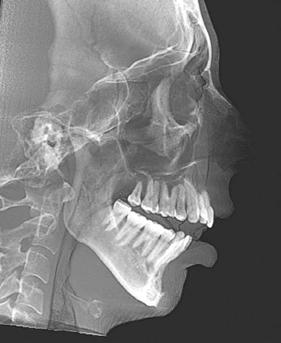

Figure 1 (left): A photo of a 69-year-old woman with a 2 mm anterior open bite and an excessive interlabial gap of 9 mm. Figure 2 (right): The sagittal slices of the above patient’s mandibular condyles reveal discontinuity of the cortical outline at the fossa and condyle (erosions). The altered condyles are flat along their path of function when she pushes her lower jaw forward to get the lips to touch in speaking, chewing, and breathing through her nose. Image captured using Dolphin® software (www.dolphinimaging.com)

12: A lateral cephalometric radiograph of a patient with excessive interlabial gap (radiograph was taken with lips postured closed). The excessive vertical has resulted in a long history of forward head posture as she pushes to close her lips. She has developed arthritis of the spine and spondylisthesis (AP vertebral instability) secondary to her consistent forward head posture. Image captured using Dolphin software (www.dolphinimaging.com)

Figure 17 (right): The lateral cephalometric radiograph, taken in repose, shows the extent of the interlabial gap, anterior open bite, and small airway. Note the silicone chin implant which was an attempt to ineffectively correct her severe skeletal discrepancy. Image captured using Dolphin software (www.dolphinimaging.com)